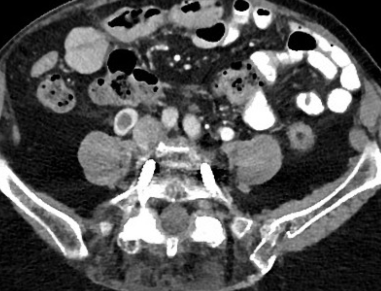

- Thrombophlébite ++

- Douleurs quadrant inférieur (droit++)

- Patientes Post-partum++

- Veine ovariene Droite++